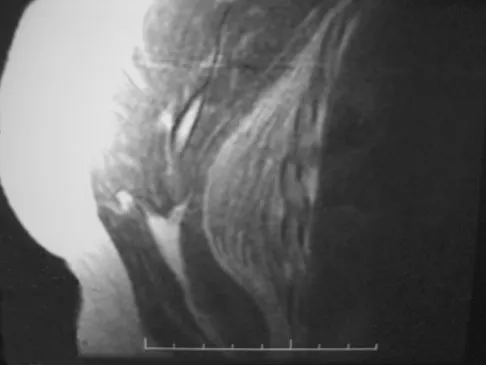

A 28-year-old man has left knee pain after a snow skiing accident. The MRI scan shown in Figure 47 reveals which of the following?

Explanation